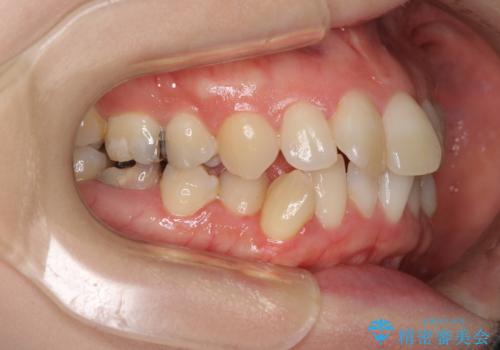

口元の突出感とデコボコがあり、上下左右の小臼歯4本を抜歯して矯正治療を行う方針としました。(右上は欠損のため計3本抜歯)

むし歯となっている歯は状態が悪く、将来的に抜歯となる可能性が高かったため、定石で抜歯させる小臼歯の代わりにむし歯となっている大臼歯を抜歯し、ワイヤー装置にて矯正治療を行うこととしました。

イレギュラーな大臼歯抜歯矯正であったため、治療期間の長期化が想定されましたが、何とか3年ちょうどで終えることができました。